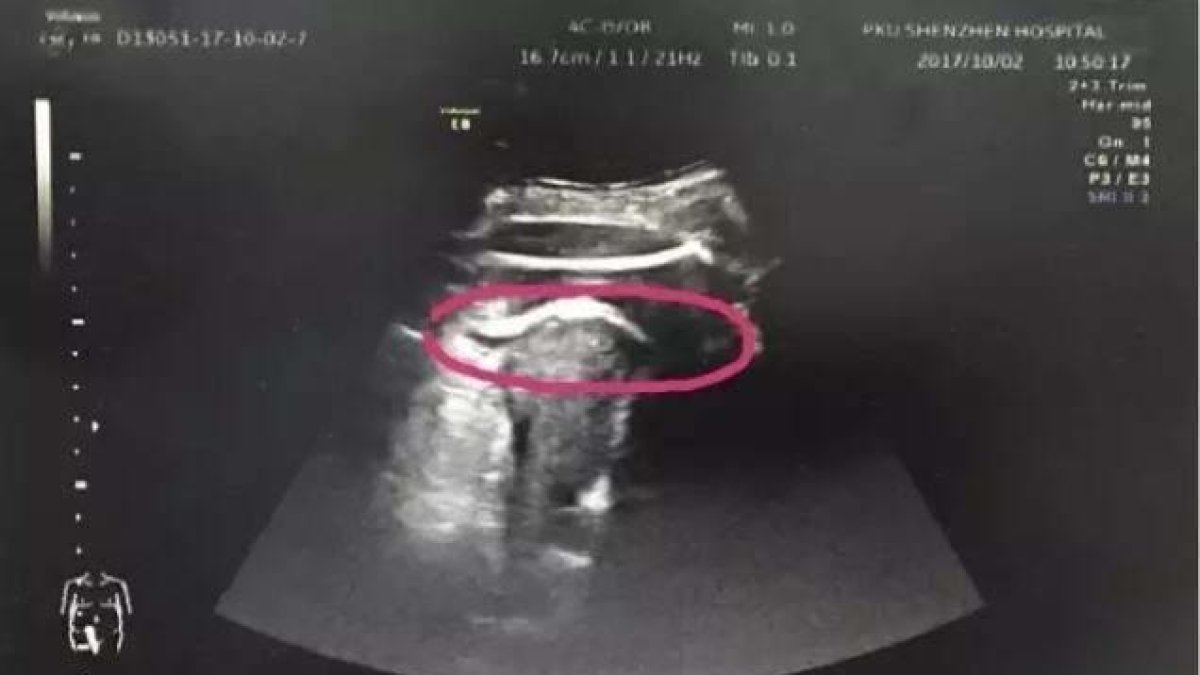

Al explicar a los doctores dónde sentía dolor, estos optaron por realizarle una ecografía para ver si se podría tratar de algún problema con el embarazo o si estos dolores tendrían alguna relación. A la prueba médica, los médicos pudieron ver cómo el útero estaba perforado y los pies del bebé salían de esta bolsa. Rápidamente, la mujer fue sometida a una cesárea de urgencia que permitió salvar la vida del bebé, que ya se encontraba en una fase lo bastante adelantada de la gestación. Esta operación también permitió salvar la vida de la madre.